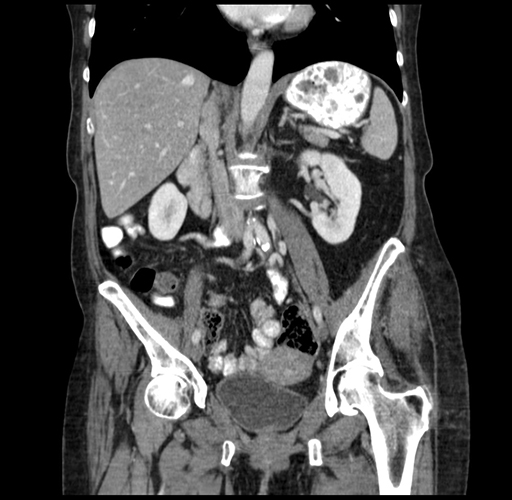

Coronal Venous